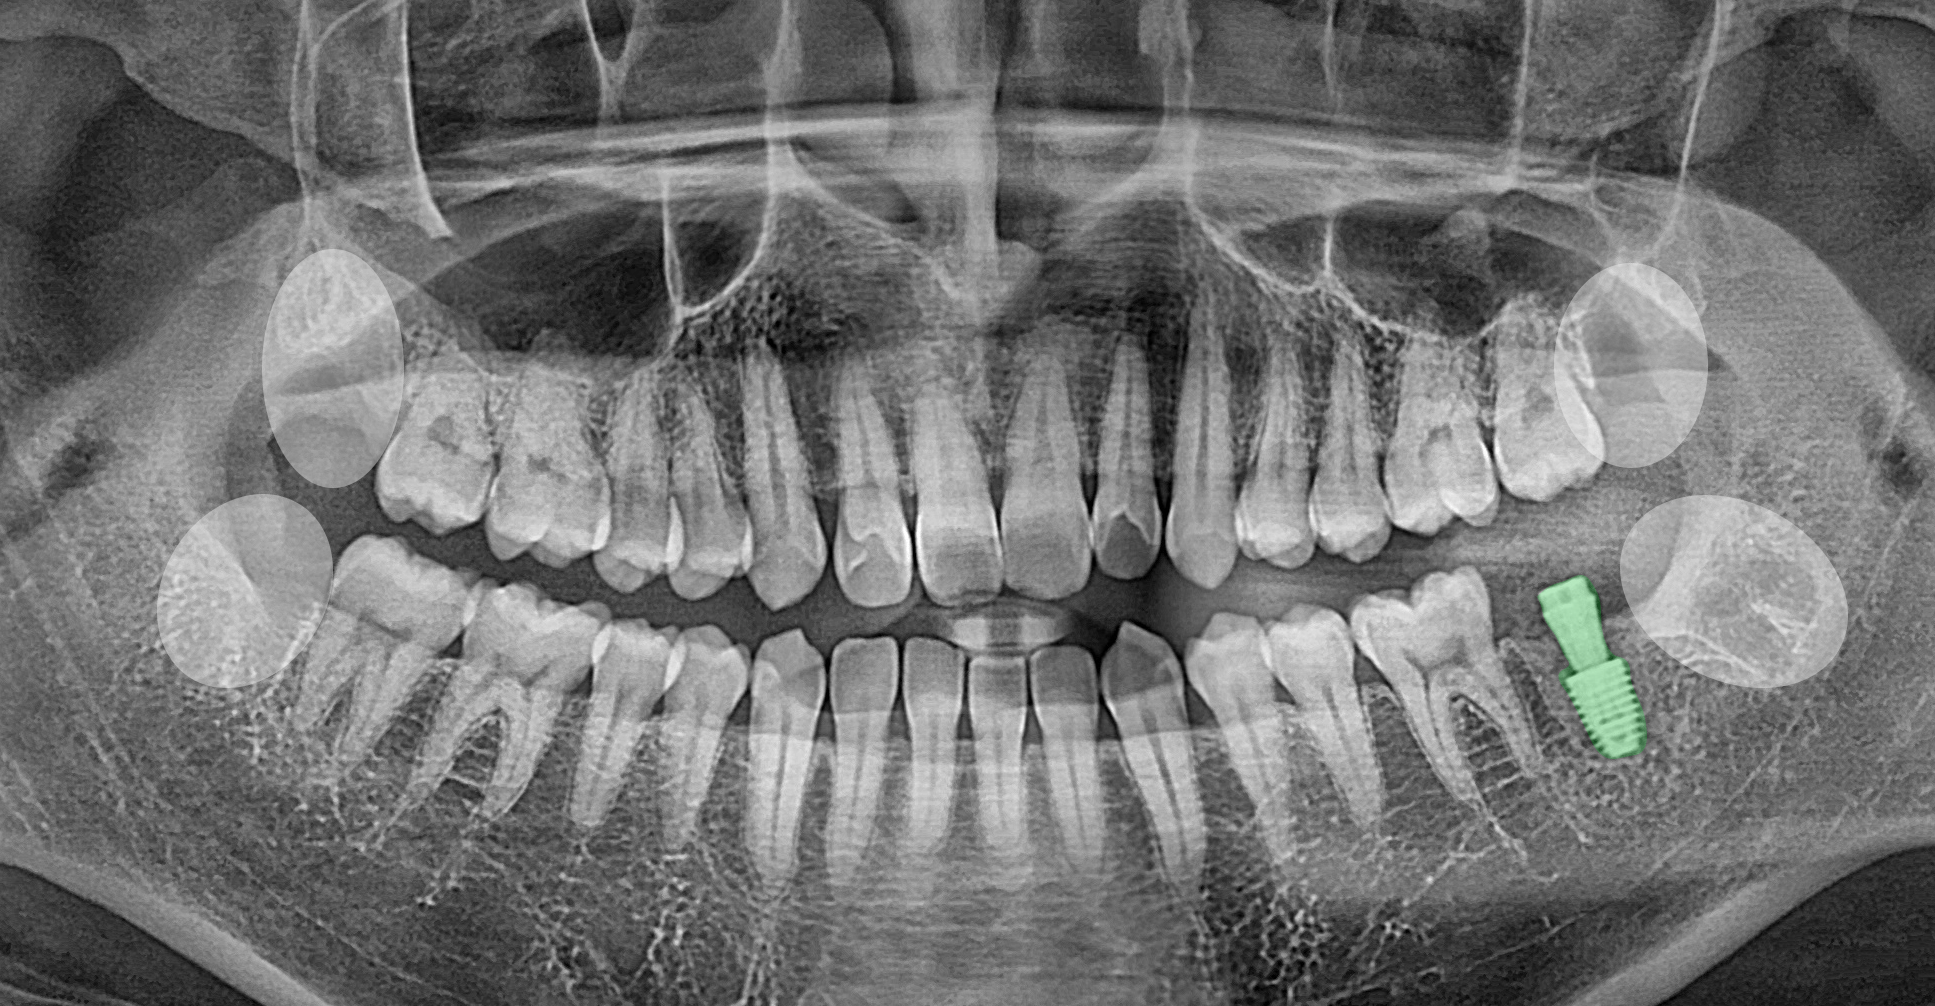

2024.11.20

4개의 사랑니와

보존이 어렵던 어금니를 발치한 후

픽스처 식립을 진행한 사진입니다.

잇몸에 염증 등 특이소견이 없었기에

당일 모든 과정을 진행할 수 있었습니다.

앞서 시행한 수술 과정에서

1/2차로 나누지 않고

일련의 과정을

한 번에 진행하였답니다.

지속적인 관찰을 통하여

골유착을 기다리고 있죠.

앞으로 2~3개월가량 더

꾸준히 지켜보면서

고정이 확인되면

보철이 장착되며 치료가 마무리됩니다.